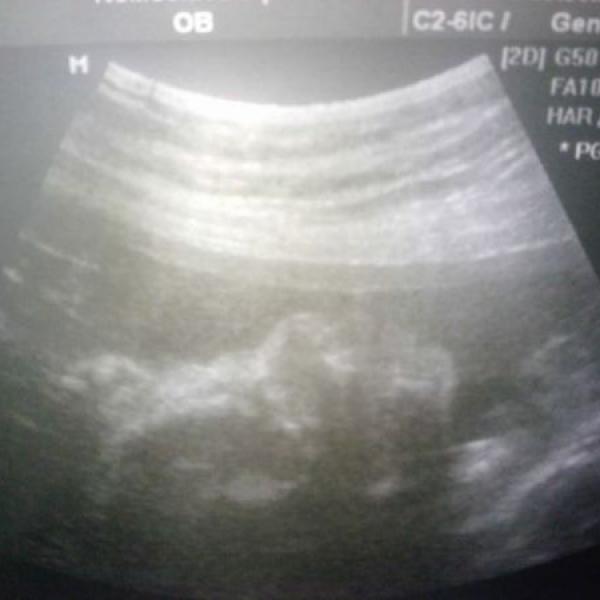

Ahojík maminky, prosím poraďte. Včera jem byla na ultrazvuku ve 30+4tt a hodně mě doktoři vyděsili tím :$$: , když mi zdělili, že malej má jen 970g a měří 27cm :jawdrop: .